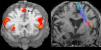

La afasia es una alteración adquirida del lenguaje debida a una lesión cerebral, que se caracteriza por errores en la producción, la denominación o la comprensión del lenguaje. Aunque la mayoría de las afasias suelen ser mixtas, desde un punto de vista práctico se clasifican en diferentes tipos según sus rasgos clínicos principales: afasia de Broca, afasia de Wernicke, afasia de conducción, afasia transcortical y alexia con o sin agrafia. Presentamos los hallazgos clínicos de los principales subtipos representándolos con casos radiológicos, y proporcionamos una revisión actualizada de la red del lenguaje con imágenes de resonancia funcional y de tractografía.

Aphasia is an acquired language disorder due to a cerebral lesion; it is characterized by errors in production, denomination, or comprehension of language. Although most aphasias are mixed, from a practical point of view they are classified into different types according to their main clinical features: Broca's aphasia, Wernicke's aphasia, conduction aphasia, transcortical aphasia, and alexia with or without agraphia. We present the clinical findings for the main subtypes of aphasia, illustrating them with imaging cases, and we provide an up-to-date review of the language network with images from functional magnetic resonance imaging and tractography.